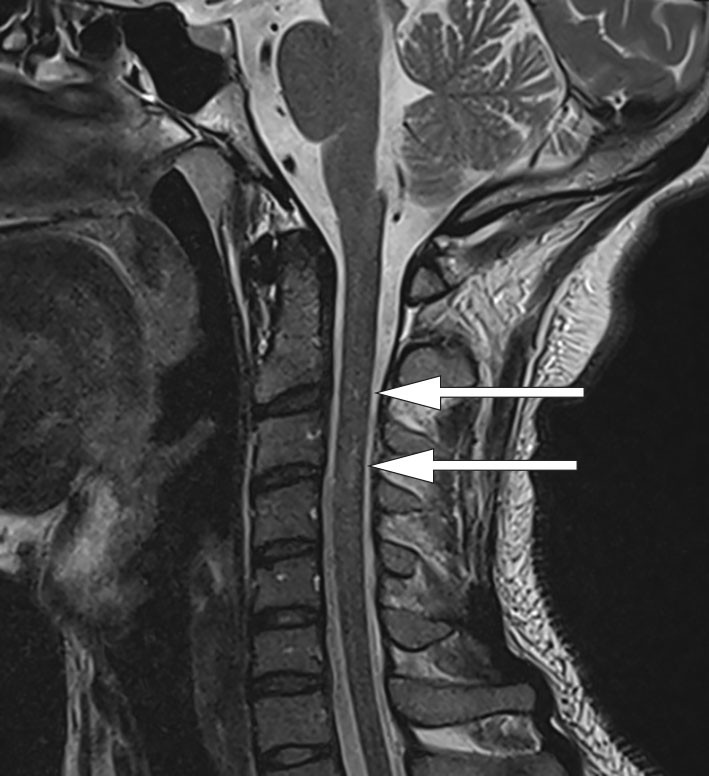

Ved kontrastforsterket MR-undersøkelse av sentralnervesystemet dag 5 viste T2-vektet bilde et subtilt høysignal i medulla på C2/C3-nivå på sagittale snitt (figur 1), og det var kontrastopplading tilsvarende bakstrengen på aksiale snitt (figur 2). Derimot var det ingen kontrastopptak langs lumbale nerverøtter eller conus medullaris.

Funnene tydet på nerveskader både i medulla og i underekstremitetene. Ettersom det ikke var forhøyet protein i spinalvæsken eller kontrastopplading lumbalt på MR-undersøkelse, var funnene ikke forenlig med Guillain-Barrés syndrom. MR-undersøkelse av ryggmargen (figur 2) viste såkalt omvendt V-tegn (inverted V-sign) eller «kaninører». Dette er benevnt som subakutt kombinert degenerasjon og er karakteristisk for demyelinisering av bakstrengen på bakgrunn av B12-mangel (5).